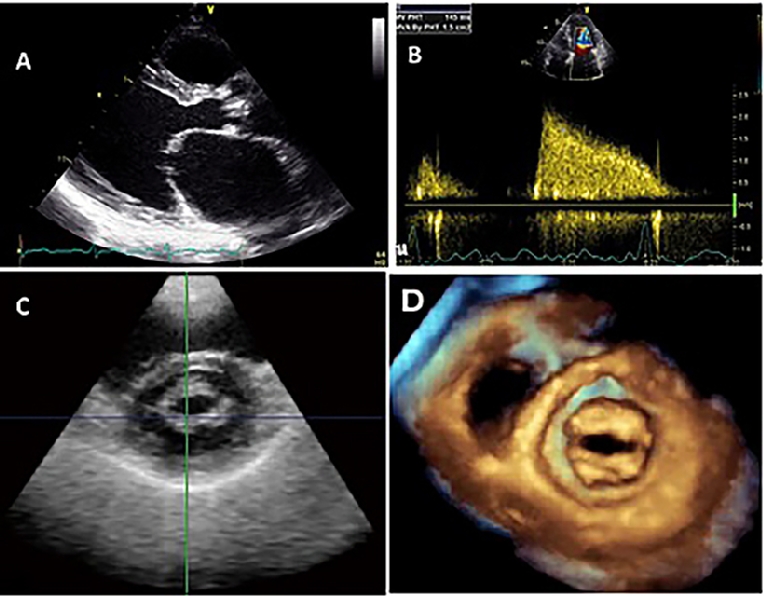

1. In the parasternal long-axis view, the main diagnostic feature in rheumatic MS is the diastolic doming or hockey-stick shape of the anterior mitral leaflet (Figure 2A). This doming is due to the reduced mobility of the valve tips compared to the base of the leaflets. The extent of doming of the anterior leaflet can be assessed subjectively or objectively by the Reid grading system [10]. The posterior mitral leaflet motion is usually restricted.

1. Measurement of mean pressure gradient across the MV in apical views. The gradient can be measured by tracing the dense outline of mitral diastolic inflow, and the mean pressure gradient is automatically calculated using the simplified Bernoulli equation = 4v2. Continuous wave Doppler is preferred (Figure 2B).

2. Measurement of MV orifice area by 2D planimetry from the parasternal short-axis view is a reliable method. Direct tracing of the mitral orifice is performed including the commissures at the level of the tips when maximal excursion of the leaflets is seen (Figure 2C).

3. Calculation of MV orifice area by pressure half-time (P1/2t) in an apical 4-chamber view using continuous wave Doppler. MVA is derived using the empirical formula: MVA = 220 / P1/2t. The continuity equation can be performed for calculation of MVA using the flow through the aortic valve and pulmonary valve with the formula: MVA = VTI LVOT x LVOT area / VTIMV Calculation of MVA using the PISA method is liable to contain errors due to multiple measurement. Both methods are rarely used unless necessary due to their significant limitations and liability to calculation errors.

Figure 2. Doming of the anterior MV leaflet in parasternal long-axis view (A), continuous Doppler tracing of MV inflow to measure the pressure gradient across it (B), 2D-planimetry of MVA obtained from parasternal short-axis view (C), and MV orifice by 3D echo (D).

Three-dimensional echocardiography is useful in enhancing the objective assessment of MV morphology from a single imaging plane [12]. It enables visualisation of the narrowest orifice of the MV through better alignment of the image plane at the mitral tips (Figure 2D). The 3D-derived MVA is accurate and reproducible with excellent interobserver and intraobserver agreement. 3D echo allows detailed characterisation of the degree of MV involvement (leaflet motion and calcification and commissural fusion) and of the subvalvular apparatus (chordate shortening and fusion, papillary muscle fibrosis, necrosis and rupture). A validated scoring system by 3D echo can be used for the decision on balloon mitral valvotomy [11]. Post balloon valvotomy, 2D planimetry of the MVA by Doppler is limited and 3D echo can be used to visualise splitting of commissures and to measure the achieved MVA.